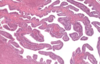

Endocrine pancreas cells

Pancreatic acini (with exocrine cells) - dark purple

Pancreatic islet (with endocfine cells) - light purple

Islet of Langerhans (endocrine pancreas), surrounded by serous acini (exocrine pancreas)

Assume that most cells in middle of islet are beta and cells at periphery of islet is alpha cells

Alpha and beta cells in islet of Langerhans

Allows differentiation bw alpha and beta cells in islet of Langerhans. Beta cells stain more purple, alpha cells stain more pink. Most cells are beta cells, especially the ones in the middle

Beta cells in pancreas

Stains the insulin that is secreted by beta cells, beta cells stain darker